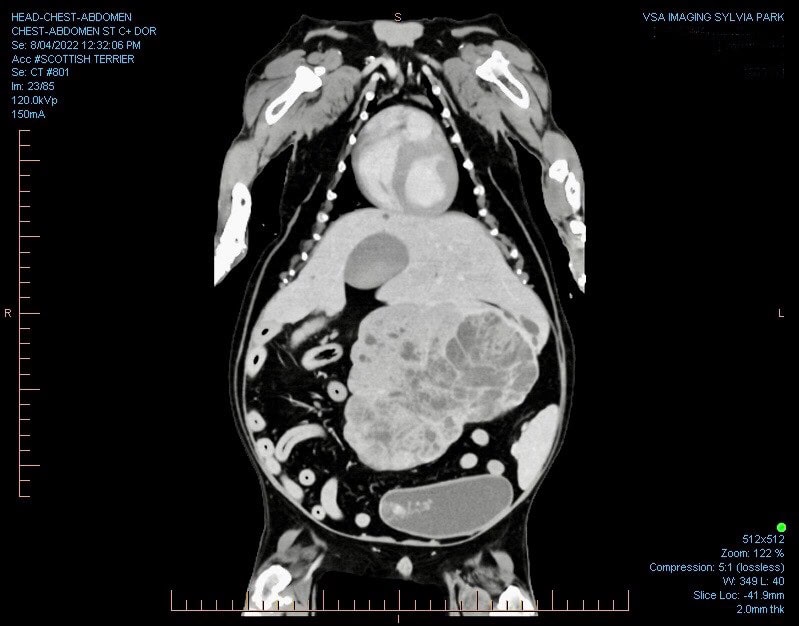

• Abdominal Tumours- Liver, Spleen, Adrenal

Diagnostic Imaging plays an important part in showing us the size of a tumour, where it is and what other areas are involved.

Generally your pet will need at least one form of diagnostic imaging before a treatment plan is discussed.  At VSA we are able to offer Ultrasounds, X-rays, CT Scans and MRIs.

The most important thing we can do with any VSA Cancer Care patient is to work up a treatment plan that individually suits them and their family.  To do this we need to have an accurate diagnosis and an understanding of the degree in which the cancer has progressed or spread.

This is where our Imaging Department comes in. During your pet’s initial consult with one of our specialist surgeons or internal medicine specialists they may recommend the need to do further imaging such as an ultrasound, CT or MRI even if you pet has already had radiographs or an ultrasound at your general practice clinic.

This form of imaging is known as “staging”. Staging helps us determine the size of a tumour and whether the cancer has spread to other parts of the body, known as metastases.

Our radiologists are experts in the interpretation of all imaging modalities, from X-rays, ultrasounds, CT and MRI. They are also able to safely obtain tissue samples by FNA and biopsies with either ultrasound or CT guidance.